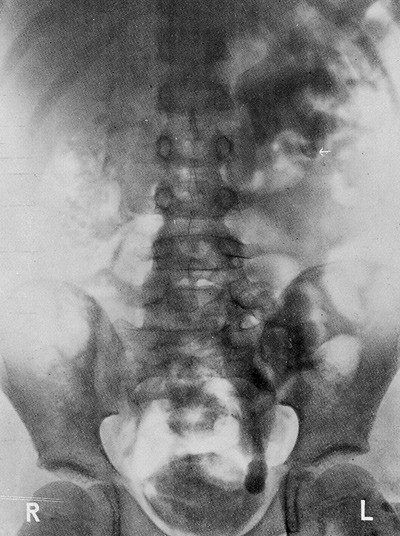

Et av spørsmålene som først melder sig når man står overfor en kronisk urinveisinfeksjon, er dette: Hvorfor er denne infeksjon så hårdnakket og langvarig? Man spør sig selv om der ved siden av infeksjonen er andre forhold som betinger kroniciteten. (...) Ved podning av urin og ved vanlig røntgenografi av nyre-urinveier vil man jo i de fleste tilfelle få sikkerhet for diagnosen sten eller tuberkulose. Vanskeligere har det vært å stille en nøiaktig diagnose hos spebarn eller småbarn hvor det dreiet sig om nyre-urinveis-deformiteter. Som så ofte ellers i medisinen er det nye diagnostiske undersøkelsesmetoder som har gitt oss muligheten av å få større innsikt på de forskjellige felter. Et sådant middel var utskillelsesurografien som i 1929 blev innført i klinikken av Roseno, Swick og von Lichtenberg. Ved injeksjon intravenøst av stoffer som utskiltes gjennem nyrene og som gav kontrast for røntgenstrålene, fikk man ved denne metode røntgenogrammer av nyrer, nyrebekken, ureteres og urinblære som tillot slutninger om disse organenes funksjon. Og disse opplysninger fikk man ved en undersøkelsesteknikk som lå langt nærmere op til de fysiologiske tilstander enn de man kunde opnå ved retrograd instrumentell urografi. At denne undersøkelsesmetode fikk den aller største betydning for pediatrien sier sig selv, idet instrumentelle retrograde urinveisundersøkelser er et stort apparat, forbundet med mange vanskeligheter hos spebarn og småbarn.